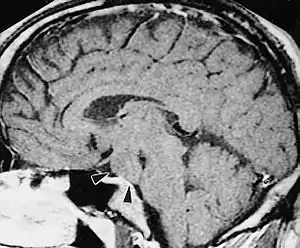

| A hypothalamic hamartoma (black arrows) on MRI | |

The tumor is difficult to detect by CT due to decreased sensitivity of the scan at the level of the sella turcica. MRI is the primary imaging modality for detection, with the lesion being of similar signal intensity to gray matter and non-enhancing with contrast. Lack of enhancement is an important imaging characteristic to help distinguish the tumor from similar masses that can occur in this region. These include germ cell tumors, granulomas of Langerhans cell histiocytosis and hypothalamic astrocytomas, as these lesions usually demonstrate at least partial uptake of contrast.[1]